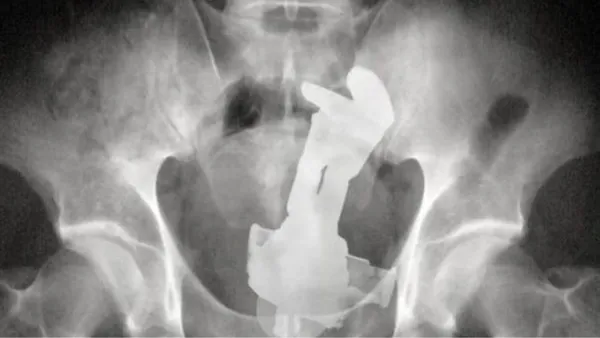

Voor het programma Jackass deed Ryan Dunn ook een duit in het (menselijke) zakje. In de eerste bioscoopfilm uit 2002 slikt hij als huis-tuin-en-keukenstunt een dinky toy door met behulp van een condoom en een handvol glijmiddel. Vervolgens meldt hij zich bij de radioloog.

De grote grap moest zijn dat er een dinky toy op de röntgenfoto te zien was en dat lukte. Na de opnames werd het autootje operatief verwijderd. De röntgenfoto mocht Dunn als trofee meenemen. Dus eind goed al goed.

Overigens is deze röntgenfoto van Dunn tegenwoordig te bewonderen in Nederland. De Nederlandse advocaat en kunstverzamelaar Aernoud Bourdrez vond de röntgenfoto namelijk zo geweldig dat hij Dunn benaderde met het voorstel de foto te ruilen voor een gifgroene DAF 46.

Dunn ging akkoord en sindsdien is de foto te bewonderen in de galerie van Bourdrez in Amsterdam. Dunn zelf is nergens meer te bewonderen. Op 20 juni 2011 werd een auto, maar dan iets groter dan een dinky toy, Dunn alsnog fataal. Hij kwam die dag om het leven toen hij ermee tegen een boom reed.

Dinky Toy